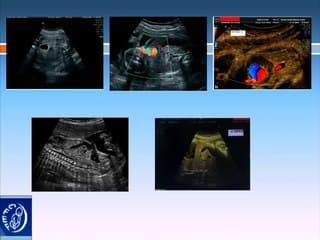

La plus grande ressource vidéo en échographie fœtale de France. Conférences, cours magistraux, démonstrations pratiques et podcasts par les experts du Collège Français d'Échographie Fœtale.

La médiathèque du Collège Français d'Échographie Fœtale (CFEF) constitue l'une des plus importantes collections de ressources vidéo dédiées à l'échographie fœtale en France. Avec plus de 3 261 vidéos, elle couvre l'ensemble des thématiques liées à la pratique échographique prénatale.

Vous y trouverez des conférences présentées lors des congrès nationaux et internationaux, des cours magistraux dispensés par des experts reconnus, des démonstrations pratiques sur des cas cliniques réels, ainsi que des podcasts et tables rondes sur les dernières avancées de la spécialité.